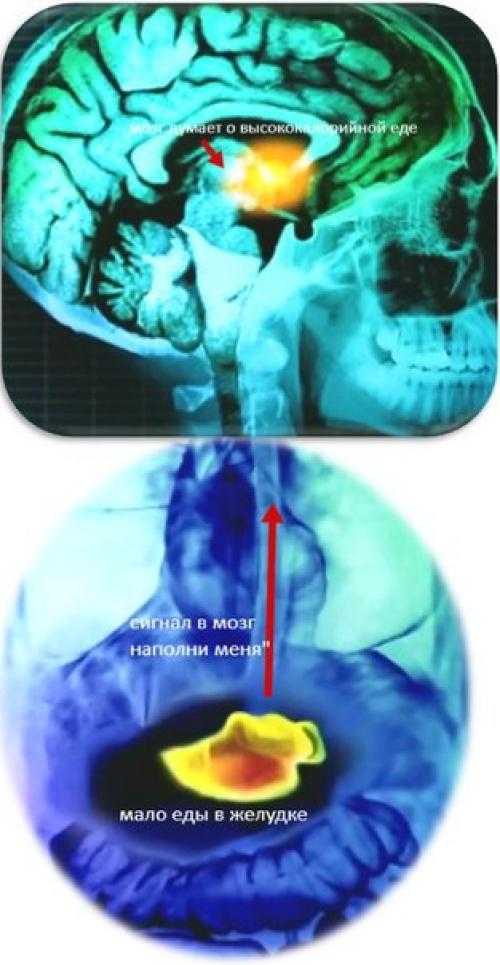

Всеми позывами охомячивания управляет высший орган нервной деятельности, мозг. Именно питательные сигналы от него заставляют человека обратить внимание на еду. В частности, после плотного завтрака (т. е. когда вы его не пропустили), мозг находится в состоянии сытости и практически никак не реагирует на еду. В случае если вы решили "Забить" на какой то из приемов пищи, мозг начинает воспалено реагировать на высококалорийную еду (сладости, шоколад, пончики и тп.

Вывод: вы можете пропустить завтрак, обед или ужин, тем самым обманув себя, однако мозг обмануть не удастся. Он всячески попытается компенсировать этот прием пищи, причем сделает сие самым "Мерзким" способом - путем мечтания о высококалорийной еде.

Гормон грелин.

Такая реакция мозга вырабатывается под воздействием гормона голода, грелин. Когда желудок пуст, он посылает сигнал в мозг - "эй хозяин, ты что там уснул? А ну ка наполни меня! Совет номер 2. смените посуду.